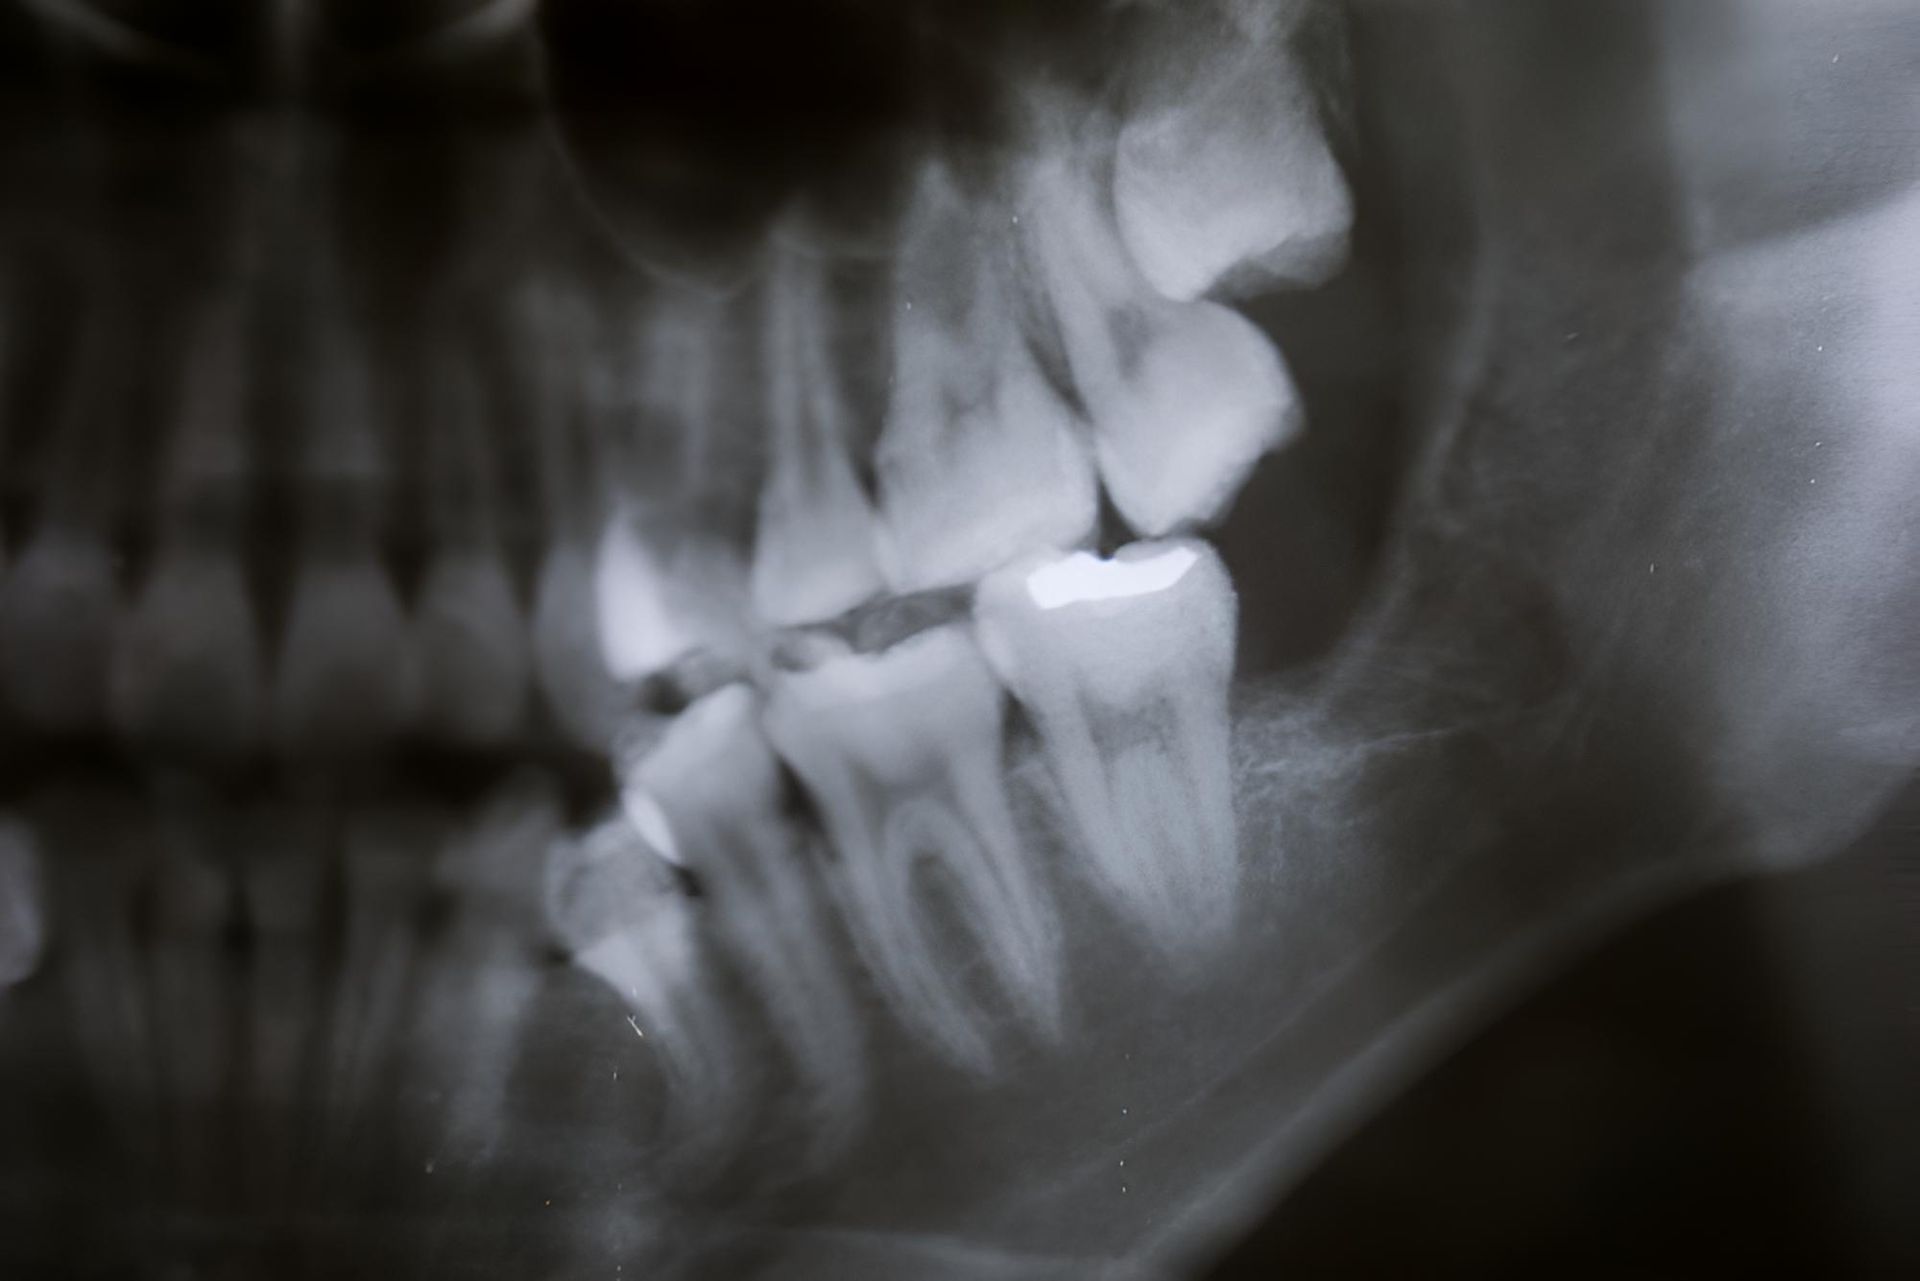

At Trower Dental, the wisdom tooth removal process begins with a clear and careful assessment. We use a combination of visual checks and imaging to understand the position of your wisdom teeth and whether they may lead to discomfort, infection, or crowding. From there, we discuss your options based on what’s best for your situation.

Wisdom teeth may need to be removed if they are causing pain, pushing against other teeth, or becoming impacted. Their position at the back of the mouth makes them harder to clean, increasing the risk of decay and gum disease. Removal is often recommended when they create pressure, inflammation, or are likely to affect nearby teeth and jaw structure. Even when not painful, preventative removal may be suggested based on dental assessments and X-rays.

What is an impacted wisdom tooth?

An impacted wisdom tooth is one that fails to fully emerge through the gum or grows in at an angle due to lack of space. This can cause pain, swelling, and lead to infections or damage to nearby teeth. In some cases, cysts can form around the impacted tooth. Impacted wisdom teeth are usually discovered during dental checkups and are commonly removed to prevent further complications and support the long-term health of surrounding teeth and gums.